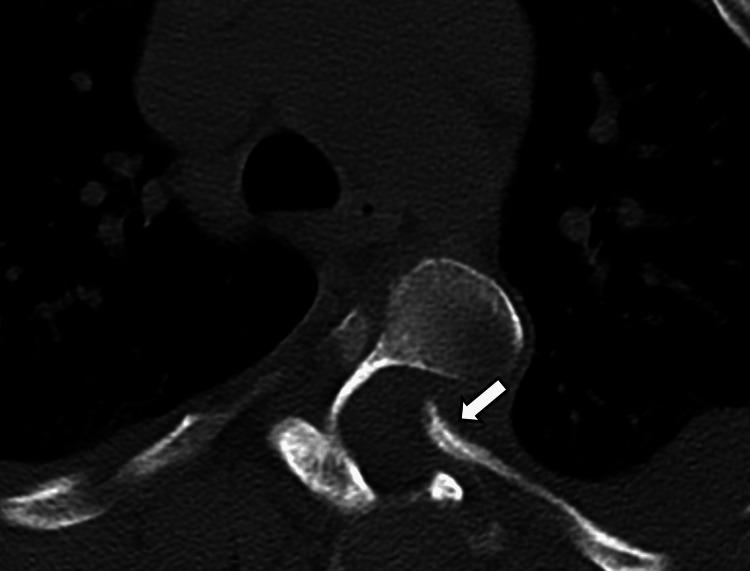

Neurofibromatosis type 1 (NF1) is frequently associated with a multitude of skeletal abnormalities including dystrophic scoliosis. A rare but severe complication of dystrophic scoliosis in NF1 is the herniation of rib heads into the spinal canal, potentially leading to devastating spinal cord compression. We present two pediatric cases of NF1-associated dystrophic scoliosis with intra-spinal herniation of rib heads. Case 1 involves a teenage male with progressive thoracolumbar scoliosis and protrusion of T10 and T11 rib heads into the spinal canal, who underwent successful posterior spinal fusion (T3-L3) with instrumentation, osteotomies, and rib head resection. Case 2 involves a teenage female with progressive thoracolumbar scoliosis and intra-spinal protrusion of T4 and T5 rib heads, who remains neurologically intact despite worsening curvature. Intra-spinal herniation of rib heads is a clinically important complication of NF1-associated dystrophic scoliosis requiring close surveillance. Familiarity with this complication is important as imaging findings may be subtle early on. Surgical management typically involves both spinal fusion and resection of rib heads to prevent neurological compromise, though timing may vary based on symptoms and progression. Multidisciplinary care is essential.

1型神经纤维瘤病(NF1)常伴有多种骨骼异常,包括营养不良性脊柱侧凸。NF1中营养不良性脊柱侧凸的一种罕见但严重的并发症是肋骨小头疝入椎管,可能导致毁灭性的脊髓压迫。我们报告两例NF1相关的营养不良性脊柱侧凸伴肋骨小头椎管内疝的儿科病例。病例1为一名青少年男性,患有进行性胸腰椎脊柱侧凸,T10和T11肋骨小头突入椎管,接受了成功的后路脊柱融合术(T3-L3),包括器械固定、截骨术和肋骨小头切除术。病例2为一名青少年女性,患有进行性胸腰椎脊柱侧凸,T4和T5肋骨小头椎管内突出,尽管脊柱侧凸加重,但神经功能仍保持完好。肋骨小头椎管内疝是NF1相关的营养不良性脊柱侧凸的一种重要临床并发症,需要密切监测。熟悉这种并发症很重要,因为早期影像学表现可能很细微。手术治疗通常包括脊柱融合和肋骨小头切除,以防止神经功能受损,不过手术时机可能因症状和病情进展而异。多学科护理至关重要。